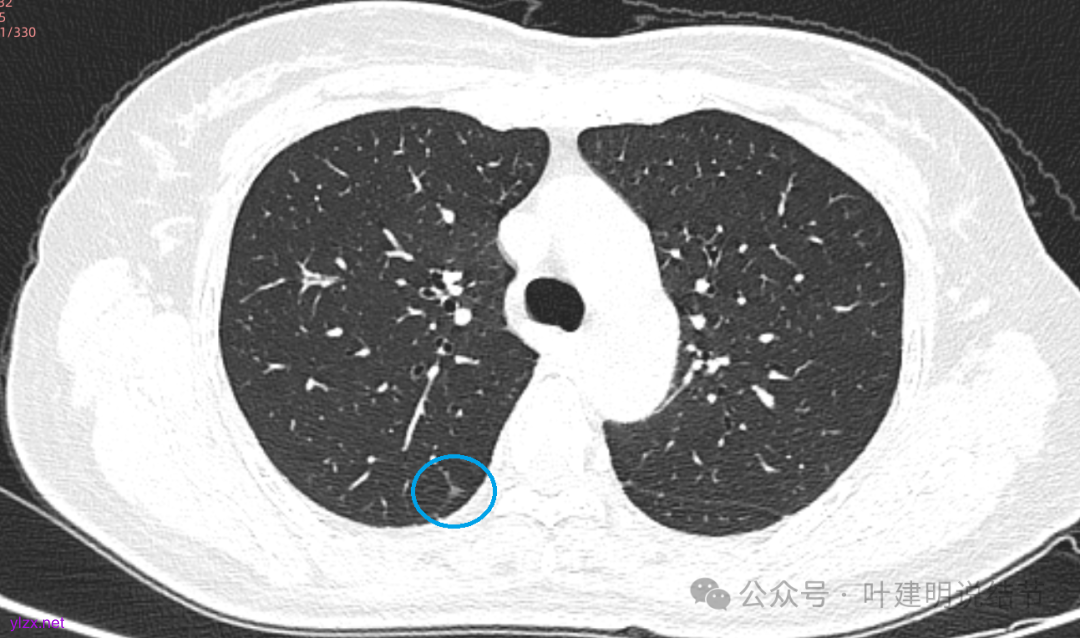

先来看2025年3月的影像:

两肺多发磨玻璃结节,我们主要看最主要的病灶有没有风险或者有没有进展就可以。我是先看2025年的,黄色的微小磨玻璃结节,密度很低,但是轮廓较为清楚,需要考虑肺泡上皮增生或者肺泡间隔增宽,严格意义上应该没有算肺癌,但是以后有可能会发展到不典型增生或者原位癌,当然也可能永远发展不到那个程度,所以目前不需要管;蓝色的到底是肺泡上皮增生还是少许慢性炎不太好确定,因为轮廓稍显模糊,但它又是磨玻璃密度,总归近期是能够随访的;橘色的密度比黄色的略高,有可能会使肺泡上皮增生或者不典型增生,目前也仍可以随访;粉色的是主病灶,位于左肺上叶,混合密度,表面毛糙,由小血管进入,单次看需要考虑微浸润性腺癌可能性较大。然后我们再来看2020年的影像,因为除了粉色的其他的都没有风险,所以不需要一一去找出来,重点关注粉色这处当时是怎样的。我们发现这个病灶5年前就有,也有小血管进入,也有表面毛糙,也是磨玻璃密度,但是当时磨玻璃当中没有实性的成分,是纯磨玻璃伴微小血管进入。对比起来看,这个病灶在5年当中略有进展,原来应该是腺体前驱病变,现在应该是原位癌或者微浸润性腺癌。那么是不是现在就到了一定得马上手术的程度呢?这个仍然可能是不同医生意见会有出入的。假如说从再随访是不是马上会转移来讲,这么小的肿瘤,发展这么慢,而且仍然含有磨玻璃成分,病理考虑与微浸润性腺癌可能性较大,应该仍然不至于说没有随访的空间。但是如果继续随反思想压力比较大,以及即便在随访后续仍然总得要开刀来说,加上病灶位置靠胸膜并不远,简单的单孔胸腔镜楔形切除就能解决问题,将有一定风险的这个病灶切了,同样是可行的。这需要你自己权衡决定。我没有办法100%给十分确切的意见。但是如果从倾向性来讲,由于是多发病灶,加上年纪还轻,风险还不是很大,稍微清一下雨6~9个月复查,有进展病风险再增加再考虑手术。意见供你参考!